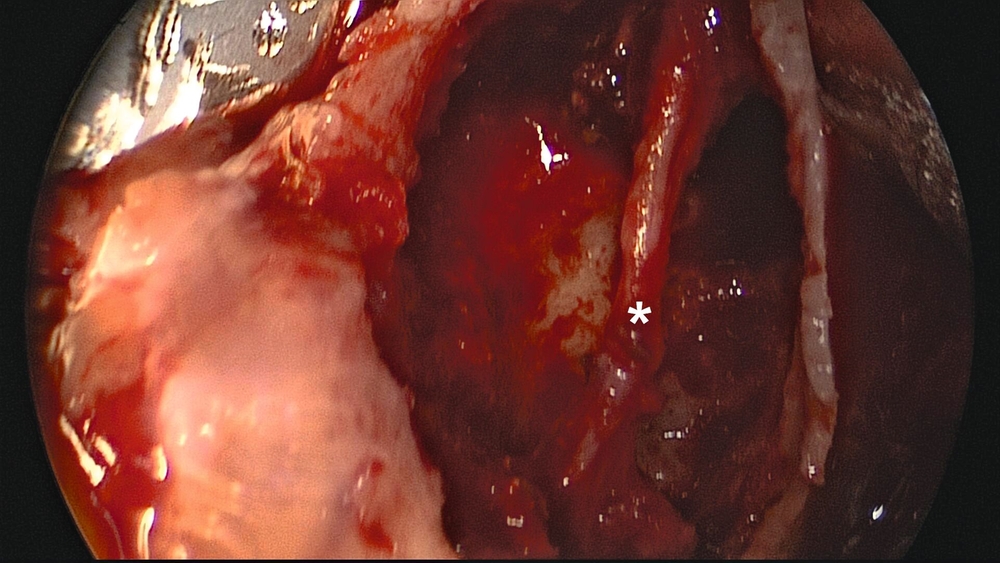

Der operative Zugang erfolgte über eine marginale Schnittführung von Zahn 36 bis 37 mit mesialer vestibulärer Entlastung sowie distaler Fortführung auf der Linea obliqua des Ramus mandibulae (Abbildung 3a). Nach Anpassen einer 8-Loch-Osteosyntheseplatte (Synthes MatrixMANDIBLE) wurde die vestibuläre Kortikalis piezochirurgisch osteotomiert. Nach Entfernung des Knochendeckels konnte die Raumforderung dargestellt und die subtotale Invagination des Nervus alveolaris inferior bestätigt werden (Abbildung 3b). Die Raumforderung konnte vollständig unter Nervschonung entfernt werden (Abbildung 3c). Die vestibuläre Kompaktaschale wurde an der zur Stabilisierung eingebrachten Osteosyntheseplatte refixiert.

Der postoperative Verlauf gestaltete sich komplikationslos. Die radiologische Kontrolle ergab keinen Anhalt für ein Residuum der Raumforderung oder für eine Fraktur des Unterkiefers. Die Osteosyntheseplatte war suffizient anliegend (Abbildungen 4a und 4b). Klinisch bestand eine geringgradige Hypästhesie im Versorgungsgebiet des Nervus alveolaris inferior. Die Patientin konnte am zweiten postoperativen Tag bei gutem Allgemeinzustand entlassen werden.

Eine Kontrolluntersuchung zwei Monate postoperativ zeigte einen unauffälligen Heilungsverlauf. Die Hypästhesie des linken Nervus alveolaris inferior war im Wärme-/Kältetest, durchgeführt mit einem NeuroSensory Analyzer (TSA-Test), noch objektivierbar, aber deutlich regredient (Abbildung 4c). Eine weitere röntgenologische Untersuchung sieben Monate nach Operation zeigte eine zunehmende Verknöcherung der Resektionshöhle ohne Rezidivverdacht. Der intraorale Befund war reizfrei und die Sensibilität nahezu vollständig wiederhergestellt (Abbildung 5).